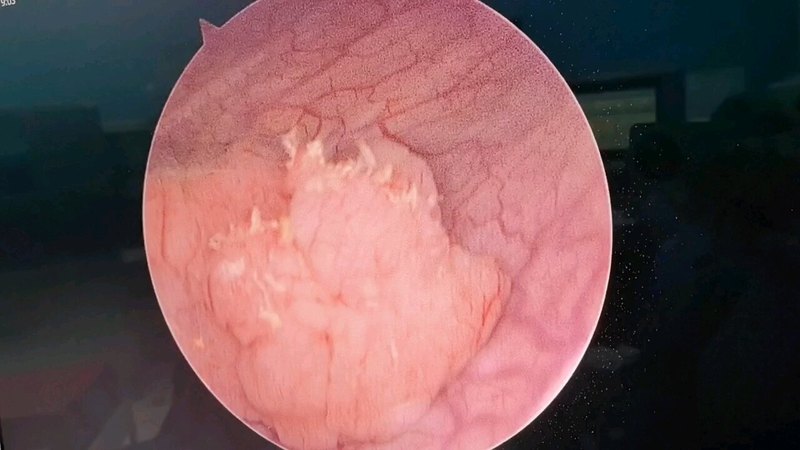

中国特色保卫膀胱【十】 超级经尿道膀胱肿瘤切除术

膀胱肿瘤铥激光整块剜除术--有效降低非肌层浸润性膀胱癌的2年复发率